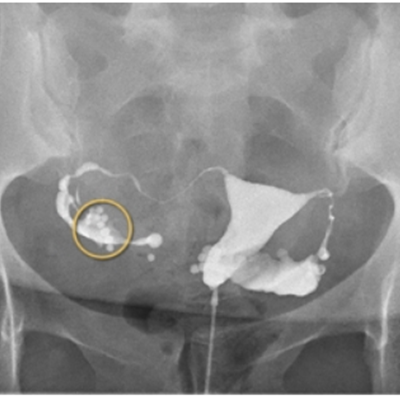

子宮卵管造影(hysterosalpingography:HSG)は、造影剤を子宮腔内に注入し、子宮内腔、卵管の陰影から子宮腔の状態、卵管の疎通性および骨盤腔内の癒着を判定する検査です。

不妊患者におけるX線像

不妊患者852例中75例(8.8%)に脈管内侵入がみられましたが、臨床症状を呈したものはなく、アレルギー反応も認められませんでした。